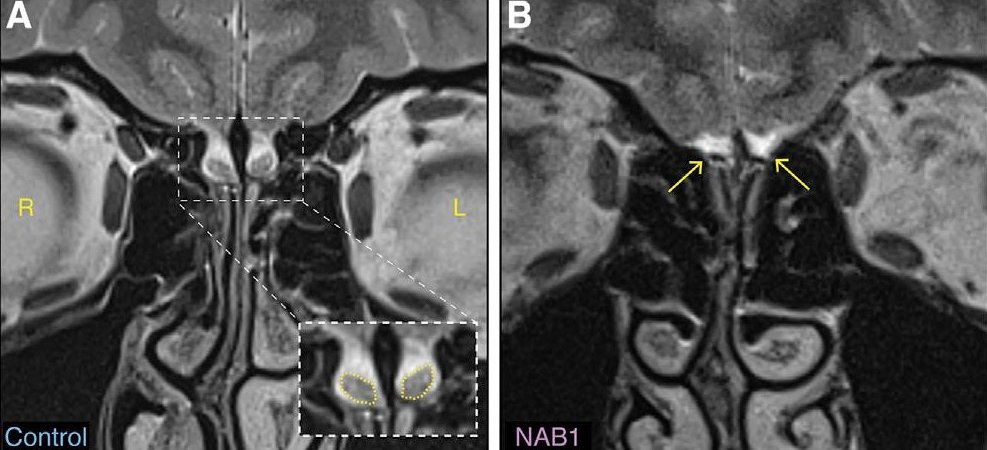

Neke žene ipak imaju uobičajeno čulo mirisa bez obzira što nemaju deo mozga za koji naučnici kažu da je presudan.